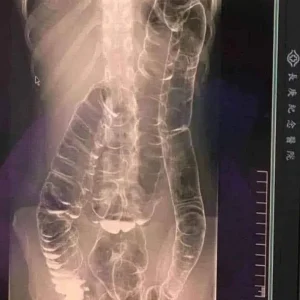

When waste accumulates in the colon due to an inefficient digestive system, it causes severe discomfort and bloating. Over time, the colon expands beyond its normal size, struggling to contain the excessive buildup of feces. In this case, medical imaging revealed a severely distended colon that had enlarged so much it reached up toward the chest, dangerously close to the heart. The stretching had nearly erased the colon’s natural folds and wrinkles, essential for its proper function. Left untreated, this condition could have led to life-threatening complications.